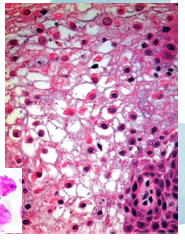

leukoedema histology

-acanthosis (thickened epithelium)

-parakeratosis (thickened parakeratin specifically)

-intracellular edema in the spinous layer

white sponge nevus histology

-parakeratosis (thickened parakeratin)

-intracellular edema in spinous layer

-perinuclear eosinophilic condensation in superficial cells (tonofilaments of mutated keratins)